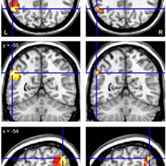

Repetition deficits in brain-injured individuals may reflect disruptions of auditory verbal short-term memory (AVSTM) (Shallice & Warrington, 1977). Disruptions of AVSTM are apparent when patients lose the phonological trace of what they have just heard, yet retain the understanding of the sentence content. An example of this is hearing a low-frequency sentence such as “The pastry cook was elated” and responding “I don’t know, but it’s something about a happy baker” (Baldo et al, 2008). Though repetition deficits were classically associated with damage to the arcuate fasciculus, recent findings with lesion symptom mapping as well as functional imaging suggest posterior superior temporal or inferior parietal regions may be involved (e.g., Paulesu et al, 1993; Buchsbaum et al, 2011). The purpose of this study was to investigate the neural correlates of ASTVM by measuring the repetition of high- and low-frequency sentences in two groups of aphasic patients with different etiologies (vascular and neurodegenerative) using similar voxel-based anatomical analyses. Methods. 115 individuals who suffered a single left hemisphere infarction with persisting aphasia were included in the study. All were native English-speaking and right-handed with no prior neurologic or psychiatric history, and had brain imaging available for lesion reconstruction. In addition, 66 individuals with primary progressive aphasia (PPA) and neuroimaging data were recruited. To assess the AVSTM deficit, all patients’ scores on the Repetition subtest of the Western Aphasia Battery were divided into high- and low-frequency sentences, (e.g., “The telephone is ringing” vs “The pastry cook was elated”). The dependent measure was the difference in accuracy between these two sets of sentences. T1-weighted, high-resolution MRI scans were also obtained for each participant. Vascular patients’ lesions were computer-reconstructed and entered into a Voxel-based Lesion Symptom Mapping (VLSM) analysis (Bates et al, 2003) along with their repetition difference scores to identify brain regions associated with poor AVSTM. Voxel-Based Morphometry (VBM) was used to identify brain regions that correlated with poor AVSTM performance in the progressive patients. Both analyses were corrected for multiple comparisons using a permutation procedure (Wilson et al., 2010). Results. For the vascular patients, there was just one cluster where lesions were significantly associated with the repetition measure. This was located in the left posterior STG and angular gyrus (extent = 7880 mm3; p = 0.040) (Figure 1). For the PPA patients, there was also only one region where grey matter volume was correlated with the repetition measure. This cluster was also centered in the left posterior STG, and also extended into the angular gyrus (extent = 6992 mm3; p = 0.017) (Figure 1). Conclusions: Using anatomical-behavioral analyses, the same focal anatomical correlates of low-frequency sentence repetition were demonstrated in aphasic individuals with two very different etiologies. The posterior superior temporal gyrus was revealed as a critical area for the repetition of low- but not high-frequency sentences, suggesting an important role for this region in auditory short-term verbal memory mechanisms.

Figure 1